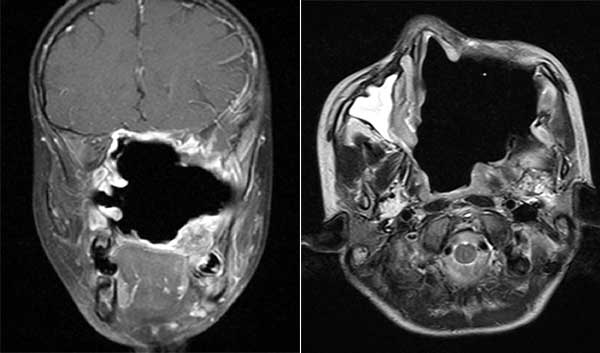

经当地医院推荐,小朱在父母的陪同下,慕名来到了我院,并找到耳鼻咽喉科邱前辉主任就诊。邱主任详细了解病情,有丰富临床经验的邱主任作出了判断:这是一例罕见的、巨大的鼻咽纤维血管瘤。检查结果显示,肿瘤如成年男性拳头一般大小,位于鼻腔、鼻咽和鼻窦,并侵入颅内和眶内(见下图)。由于与重要的器官(视神经、颈内动脉、脑干)毗邻,病情已不容耽搁,需尽快手术治疗。

术前影像(MR轴位)